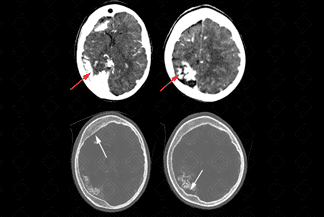

Texto alternativo para a imagem Créditos: Dra. Elazir Mota - Rio de Janeiro/RJ

Descrição da imagem: Tomografia computadorizada do crânio. Extensas calcificações girais na substância branca subcortical (setas vermelhas), em associação com atrofia no hemisfério cerebral direito onde há espessamento compensatório da díploe (setas brancas). Na janela óssea vemos com melhor nitidez as áreas de calcificação no hemisfério cerebral direito.

• Tomografia computadorizada do crânio: C omo achados de imagem, observam-se as calcificações girais (calcificações em trilho de trem), realce leptomeníngeo, atrofia do hemisfério cerebral, hiperpneumatização dos seios paranasais e díploe espessada;